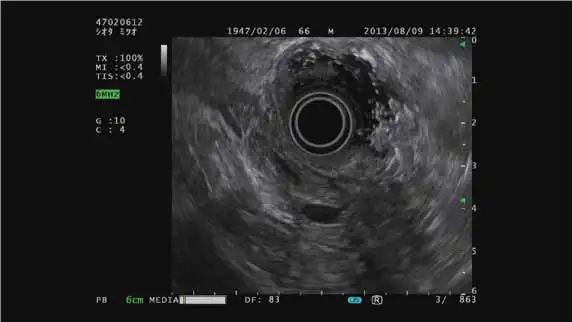

电子环形扫描

与电子环扫超声内镜配套使用

COLOR FLOW模式 THE-R模式 ELST模式